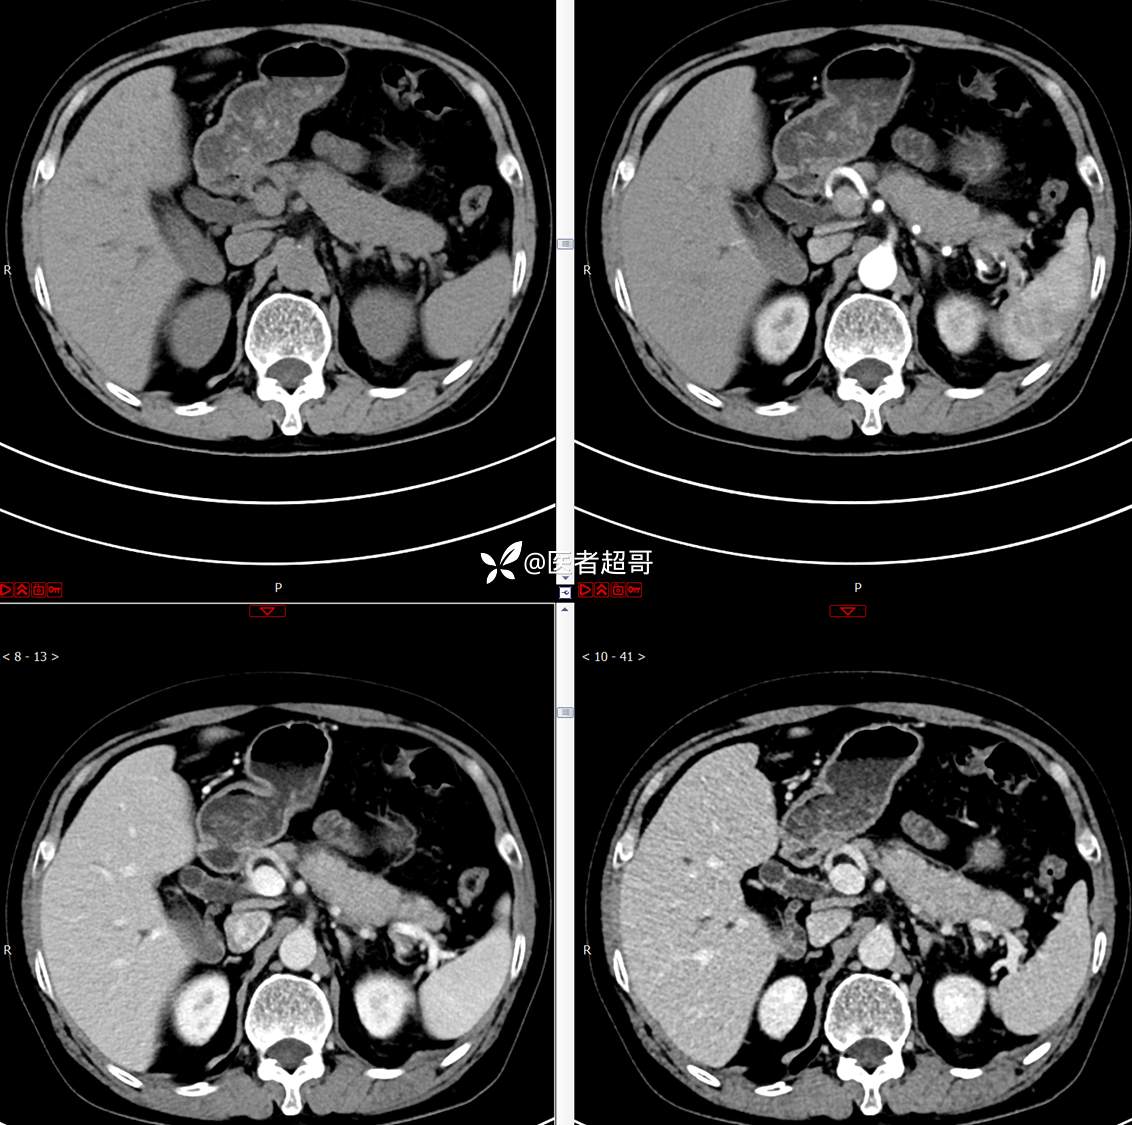

【影诊笔记772】腹痛就诊,发现肾脏病变,CT、MRI齐全,请高诊!

主 诉:间断腹痛15天

现病史:患者15天前无明显原因及诱因出现腹部疼痛不适,呈间断性钝痛,右下腹为著,无尿频、尿急、尿不尽,无发热、寒战,无腹胀。于市中心卫生院住院治疗,超声示:胰头低回声包块,胆系扩张,左肾囊肿,胆囊壁毛糙,胆囊内胆汁淤积。患者为求进一步诊治,遂以“肾盂肿瘤”收入院,患者自发病以来,神志清,精神可,饮食睡眠可,大便无明显异常,近期体重无明显增减。